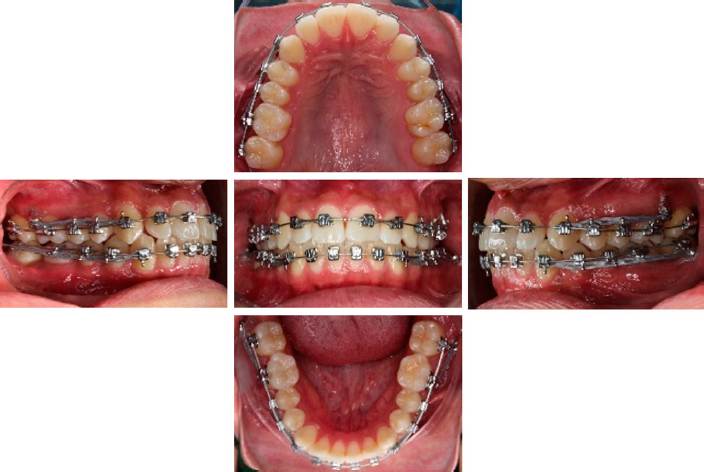

Se cementaron brackets de autoligado pasivo ranura 0.022" (Easy-K) y tubos de cementado directo en primeros y segundos molares superiores e inferiores. Bajo anestesia local se colocaron mini-implantes en cresta infracigomática y repisa mandibular de ambos lados y se realizó carga inmediata de los implantes con cadena elástica corta que iba desde el bracket del canino de cada cuadrante a su implante correspondiente con una fuerza de 50 gramos. Una vez instalada la aparatología, se remitió al paciente a extracción de los dientes 18, 28, 38 y 48.

La biomecánica consistió en distalizar la arcada superior e inferior con los dispositivos de anclaje temporal desde la fase inicial del tratamiento con cadenas elásticas medianas que se colocaron desde el implante al bracket de los caninos de cada uno de los cuadrantes (Figura 4). Se empleó una fuerza de 150-200 gramos. La cadena elástica se cambió cada dos semanas a lo largo de todo el tratamiento. Se observaron espacios entre caninos y laterales superiores de cada lado. En la fase de trabajo se colocaron ganchos crimpables en un arco de acero inoxidable 0.019" x 0.025" entre canino y lateral de cada lado y se colocó cadena elástica que iba desde el mini-implante al gancho crimpable correspondiente a cada lado, tanto en arcada superior como inferior. Para lograr mayor cierre de estos espacios, se colocó cadena elástica desde el mini-implante al bracket del canino, pasándola por la parte incisal del bracket de los cuatro incisivos superiores y volviéndola a colocar al canino contralateral y posteriormente al implante contra-lateral. En la fase de finalización, se retiraron los mini implantes, se colocó arco multitrenzado de acero 0.019" x 0.025" en inferior y arco de acero inoxidable 0.019" x 0.025" en superior.

Se utilizó la siguiente secuencia de arcos durante el tratamiento: fase inicial arcos NiTi 0.014", NiTi 0.018", Thermal NiTi 0.016" x 0.022", Thermal NiTi 0.017" x 0.025"; fase de trabajo Thermal NiTi 0.019" x 0.025", acero Inoxidable 0.019" x 0.025"; finalización multitrenzado inferior 0.019" x 0.025" acero Inoxidable superior 0.019" x 0.025" y elásticos de asentamiento "N" invertida 3/16" 2 Oz. de canino inferior a canino superior, primer premolar inferior y primer premolar superior de ambos lados, elástico en "M" V/ 2 Oz de segundo premolar inferior a segundo premolar superior, primer molar inferior, primer molar superior, segundo molar inferior de ambos lados. Se retiró la aparatología fija con pinzas quita Brackets y se eliminó el exceso de resina con pinzas con punta de titanio y posteriormente con fresa multi-hoja de alta velocidad con irrigación y pulido con discos soflex. Se colocó retenedor removible circunferencial superior y retenedor fijo inferior de 3 a 3 elaborado con alambre respond 0.017". Por último, se realizó toma de ortopantomografía y lateral de cráneo (Figura 5) y sobreimposición cefalométrica (Figura 6).